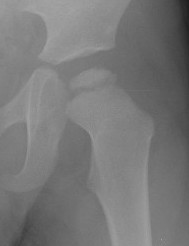

Herring Lateral Pillar

AP xray when disease in fragmentation / divide femoral head into 3 pillars

- lateral (25%)

- medial (25%)

- central (50%)

Group A

- no lateral pillar collapse or radiolucency

- all become Stuhlberg 1 & 2

Group B

- > 50% of lateral pillar height maintained

- outcome depends on age

- < age 9 almost all become Stuhlberg I and II

- > age 9 30% become Stuhlberg II / 70% become Stuhlberg III or IV

Group C

- pillar < 50% normal height

- majority do poorly